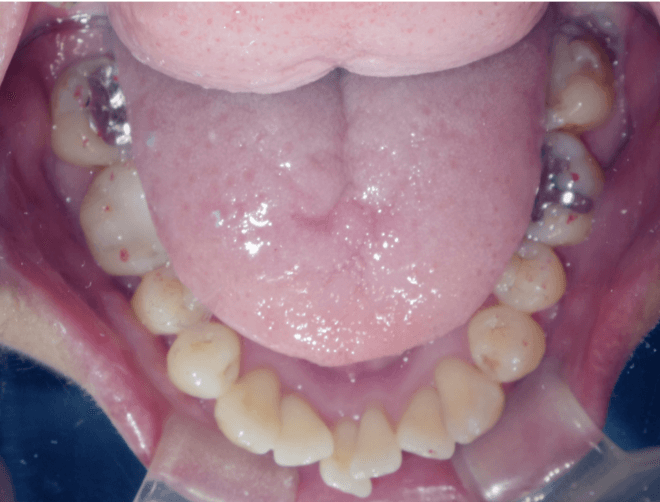

叢生(軽度)

BEFORE

AFTER

担当医コメント

上下に軽度の叢生がある。IPRと歯列の拡大で改善可能と考えインビザラインで治療を行うことにしました。

IPRは被せ物や銀歯の部位に集中させて、歯にかかる負担をなるべく少なくなるように計画した

治療の概要

年齢/性別

26歳 女性

主訴

上下の歯並びが気になる

リスク

歯肉退縮が起こる可能性がある。

費用

82万円(矯正費用)

期間

1 5 ヶ月

術前

術中

術後